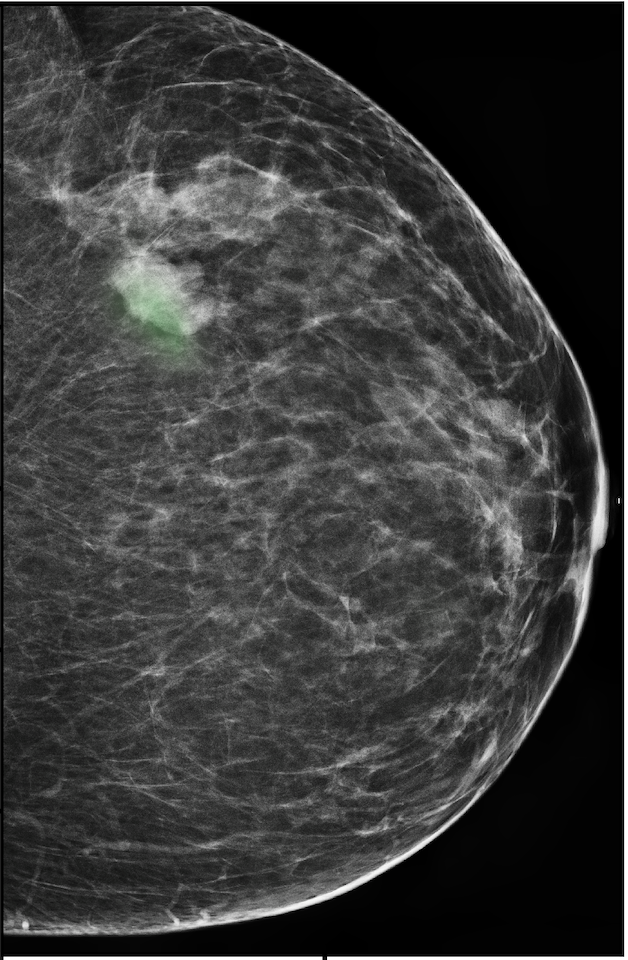

To evaluate the localization performance of GMIC, we select the model with the highest DSC for malignancy localization using the validation set. During inference, we upsample saliency maps using nearest neighbour interpolation to match the resolution of the input image. Our best localization model achieves a mean test DSC of 0.325 (std:0.231) for localization of malignant lesions and 0.240 (std:0.175) for localization of benign lesions. The best localization model achieves an AUC of 0.886/0.78 on classifying malignant/benign lesions. We observe that localization and classification performance are not perfectly correlated. The trade-off between classification and localization has been discussed in the weakly supervised object detection literature [15, 62, 82].

In Figure 7, we visualize saliency maps for four samples selected from the test set. In the first two examples, the saliency maps are highly activated on the annotated lesions, suggesting that our model is able to detect suspicious lesions without pixel-level supervision. Moreover, the attention is highly concentrated on ROI patches that overlap with the annotated lesions. In the third example, the saliency map for benign findings identifies three abnormalities. Although only the top abnormality was escalated for biopsy and hence annotated by radiologists, the radiologist’s report confirms that the two non-biopsied findings have a high probability of benignity and a low probability of malignancy. In the fourth example, we illustrate a case when there is some level of disagreement between our model and the annotation in the dataset. The malignancy saliency map only highlights part of a large malignant lesion with segmental coarse heterogeneous calcifications. This behavior is related to the design of : a fixed pooling threshold cannot be optimal for all sizes of ROI. The impact of is further studied in 3.6. This example also illustrates that while human experts are asked to annotate the entire lesion, CNNs tend to emphasize only the most informative regions. While no benign lesion is present, the benign saliency map still highlights regions similar to that in the malignancy saliency map, but with a lower probability than the malignancy saliency map. In fact, calcifications with this morphology and distribution can also result from benign pathophysiology [42].